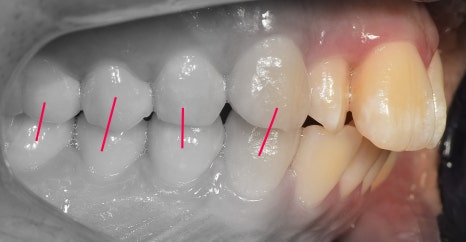

측면에서는 크게 2가지를 느낄 수 있습니다.

- 전치부 치아들의 치축, 전방 뻐드러짐

- 1치대 1치의 관계

*정상이라면, 1치대 2치의 관계를 가져야 됩니다.

또한, 측절치 및 송곳니의 총생들도 같이

관찰을 할 수 있습니다.